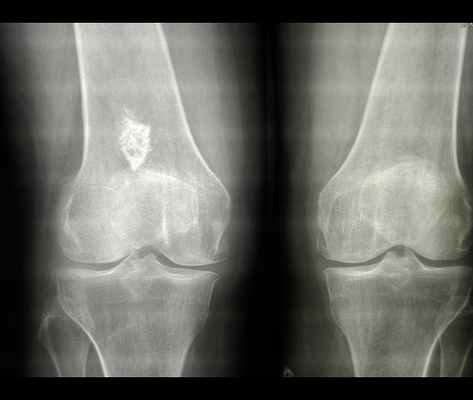

Остеосклероз коленного сустава

Такой диагноз, как остеосклероз коленного сустава чаще ставится лицам пожилого возраста. У них обычно присутствует целый комплекс проблем, связанных с опорно-двигательным аппаратом. Это артроз, остеомаляция, остеопороз, искривление костей и т.д. Но и в молодом возрасте остеосклероз вполне возможен. Особенно, если пациент ведет сидячий малоподвижный образ жизни и обладает внушительной избыточной массой тела.

Диагностировать остеосклероз коленного сустава 1-ой степени можно только с помощью рентгенографического снимка. На нем будут видны отдельные очаги и пятна. Эти области отличаются нестабильностью структуры костной ткани, могут быть заполнены фиброзными волокнами или отложениями солей кальция.